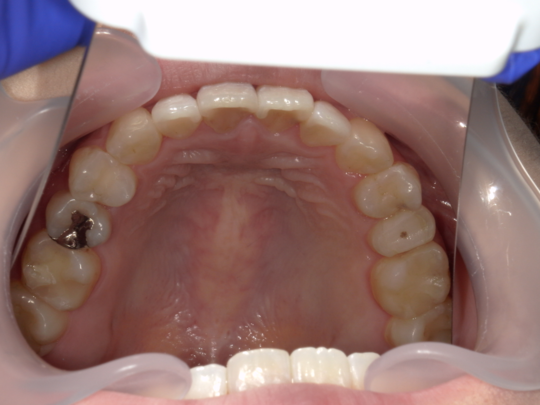

治療後

治療の副作用(リスク)歯の動き方には個人差があり、予想された治療期間が延長する可能性があります。。マウスピースの使用状況、矯正歯科治療には患者さんの協力が必要であり、それらが治療結果や治療期間に影響します